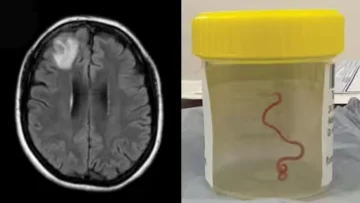

Desconcertados, los médicos realizaron una resonancia magnética a una mujer australiana de 64 años después de que comenzara a sufrir lapsos de memoria y notaron una "lesión atípica" en el frente de su cerebro.

Era una lombriz de ocho centímetros llamada Ophidascaris robertsi, que según investigadores son parásitos comunes en canguros y pitones diamantina pero no en humanos.